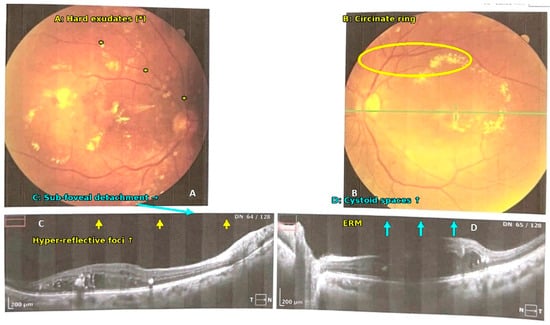

2.6. Ophthalmic Evaluation

2.7. Optical Coherence Tomography